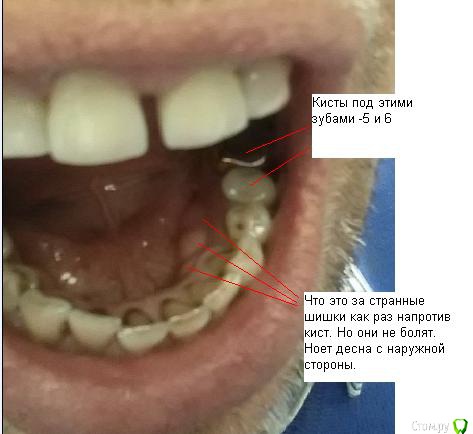

SergeySergey Опубликовано 16 октября, 2015 Поделиться Опубликовано 16 октября, 2015 Киста - что делать ? Заныла десна под 5 и 6 зубом, сделал рентген, результат - киста под 2-мя зубами 5 и 6 и еще киста между корнями у 6-ки.5 зуб болезненно реагирует на постукивания. Хирург и мой постоянный лечащий врач-терапевт говорят - нужно удалять два зуба и кисту, лечить не получится и обосновывают следующим:Проблема что 5 зуб со штифтом и вытащит штифт не возможно, а 6 проблемный в плане перелечивания, так как в канале есть инородное тело (возможно фрагмент инструмента), достать нереально а очаг как раз на верхушке этого корня, передние каналы 6 зуба тоже плохие (не видны), скорее всего не проходимы. Вероятно лечился резорцин-формалиновым методом и очень давно (1995-97 гг) Еще в другом месте врач-терапевт консультировал и говорит - не удалять а лечить все вопросы решаемые - штифт из 5-ки можно извлечь, если не извлечется штифт, то хирург доберется к кисте через челюсть, а 6-ку каналы можно вскрыть. и все вылечить за несколько месяцев и несколько посещений. Ваше мнение ? Что делать идти не к своему врачу а к тому который возьмется или удалять как говорить мой врач и хирург ? Ссылка на комментарий

shishok Опубликовано 16 октября, 2015 Поделиться Опубликовано 16 октября, 2015 Шишки на десне изнутри-экзостозы(нормальные анатомические образования).Не беспокойтесь. Ссылка на комментарий